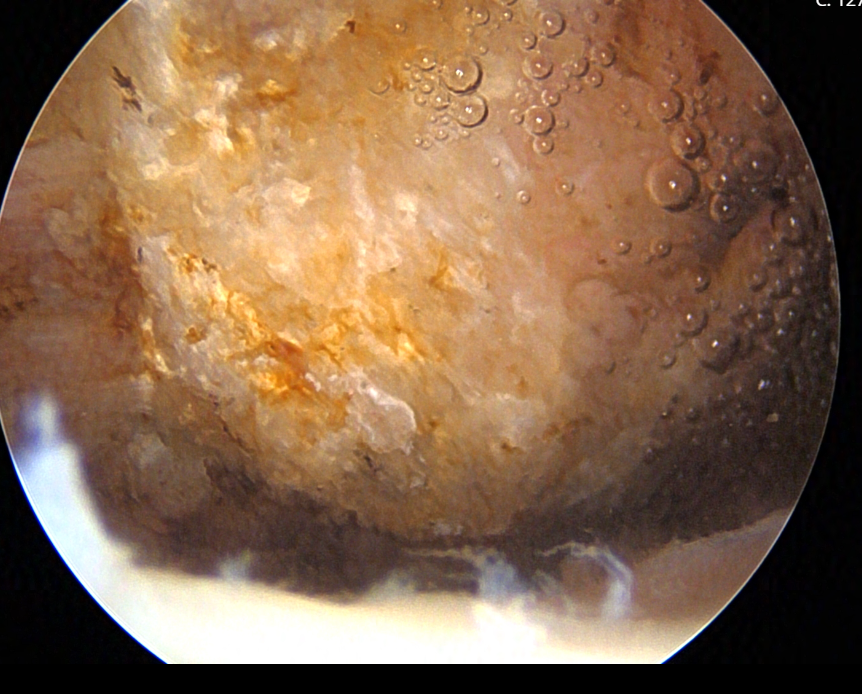

Subacromial Decompression

In a typical shoulder arthroscopy procedure, Dr. Cirino may perform several different types of repairs, depending on the diagnosis. Rotator cuff repair is one of the most common procedures performed arthroscopically. Dr. Cirino reattaches the torn tendon to the bone using suture anchors, which are small devices that hold the tendon in place during the healing process. Any bone spurs that may have caused or contributed to the tendon tear are debrided. The long head of the biceps tendon, located beneath the rotator cuff, is often repaired as part of the procedure.